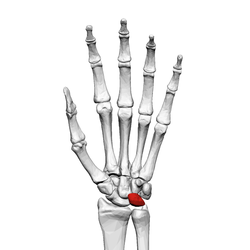

![]() Left hand anterior view (palmar view). Lunate bone shown in red. | |

The lunate bone (semilunar bone) is a carpal bone in the human hand. It is distinguished by its deep concavity and crescentic outline. It is situated in the center of the proximal row carpal bones, which lie between the ulna and radius and the hand. The lunate carpal bone is situated between the lateral scaphoid bone and medial triquetral bone.

The lunate is a crescent-shaped carpal bone found within the hand. The lunate is found within the proximal row of carpal bones. Proximally, it abuts the radius. Laterally, it articulates with the scaphoid, medially with the triquetral, and distally with the capitate. The lunate also articulates on its distal and medial surface with the hamate bone.[1]:708[2]

Lunate bone of the left hand (shown in red). Animation.